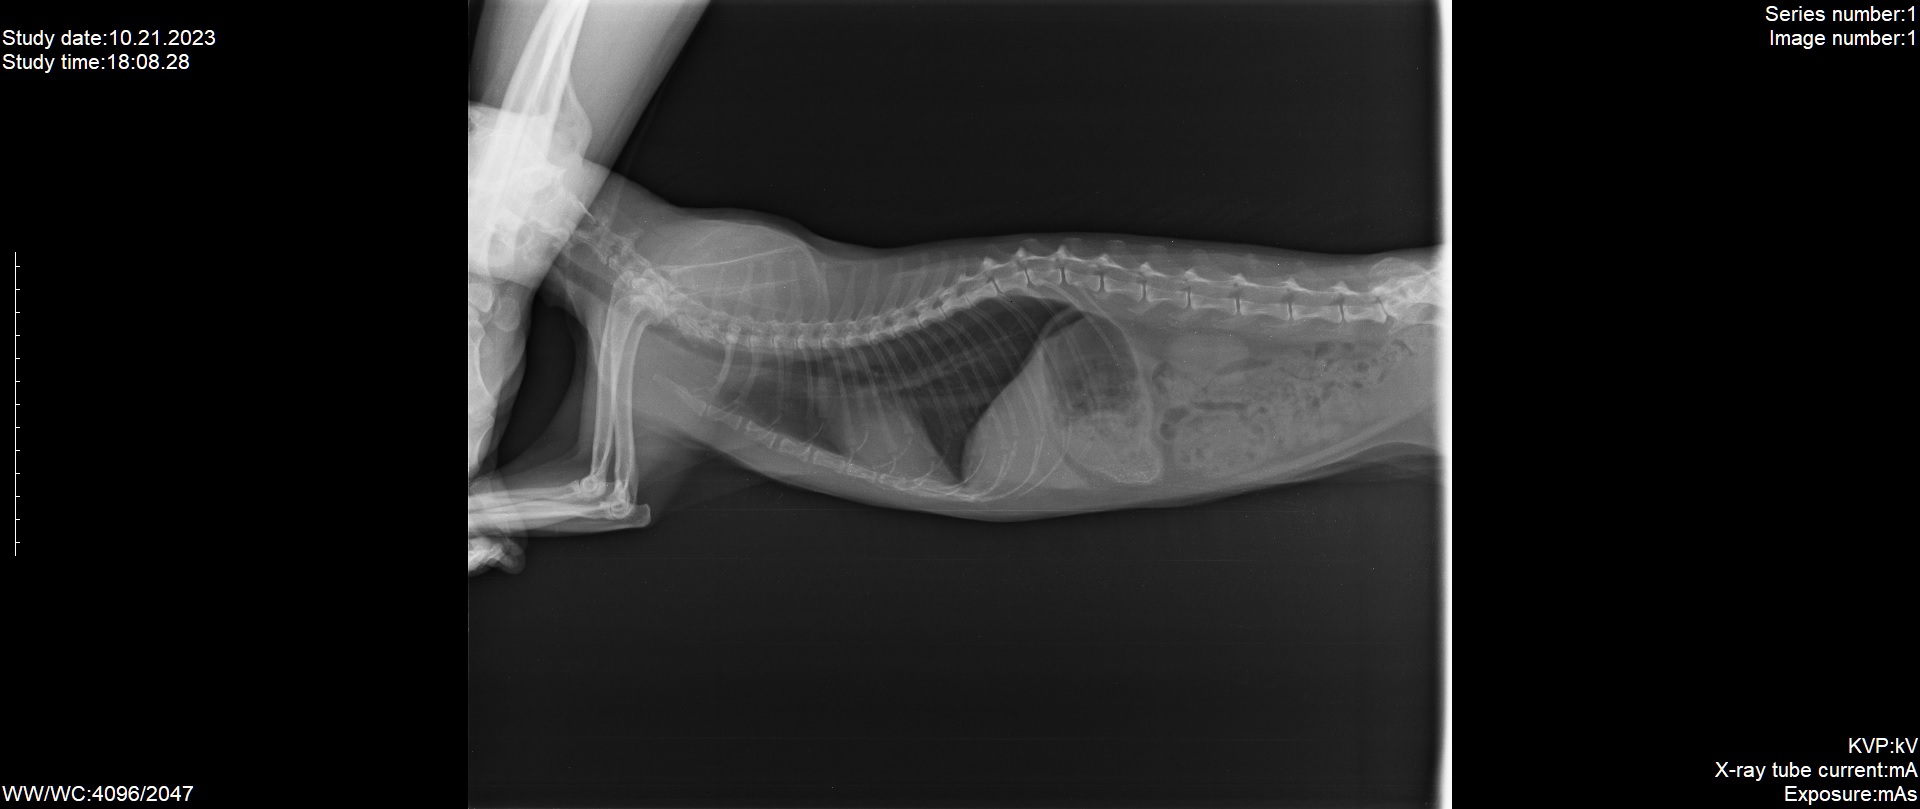

Истончение костей у кошек: причины и решения

Раздел: Мудрость в объективе